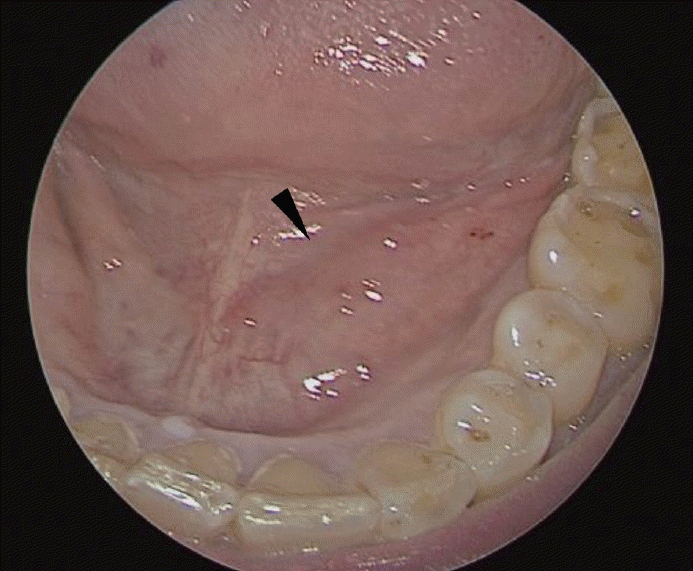

Fig. 1.

Figure shows an endoscopic photograph of the patient’s oral cavity. There is swelling on the left floor of the mouth compared to the right side (arrowhead).